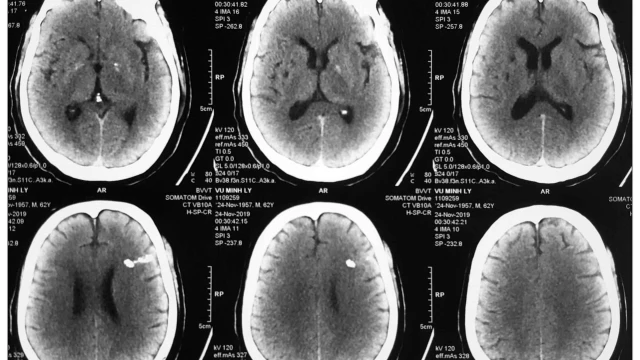

Chụp cắt lớp vi tính tưới máu não được chỉ định cho những trường hợp có nghi ngờ tổn thương não hoặc bất thường về hệ mạch máu nuôi dưỡng cơ quan này. Khi tiến hành, chuyên gia y tế sẽ kết hợp đồng thời việc dùng thuốc cản quang và phát tia X để ghi lại hình ảnh tại khu vực cần kiểm tra.